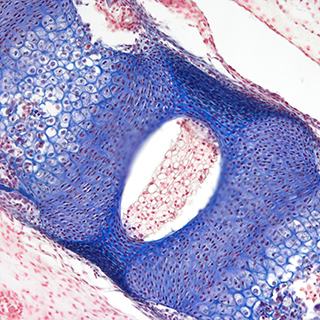

Dhyana 400DC(簡稱:400DC)是一款前照式彩色sCMOS 相機。它兼具科研級靈敏度和真實色彩還原能力,具有寬闊的視野和卓越的動態范圍,即使在弱光下也能拍攝高質量彩色圖像。

采用高靈敏彩色sCMOS圖像芯片,兼具科研級的靈敏度和真實色彩還原能力,無論明場還是暗場拍攝,都能清晰拍攝細節豐富的彩色圖像。